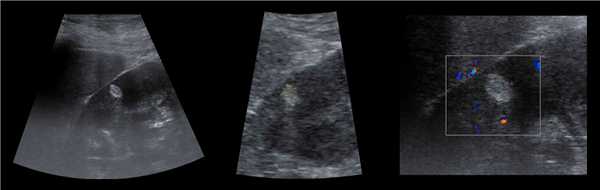

В марте 2002 г. в связи с эпизодом лейкоцитурии лечился у нефролога; при контрольном УЗИ впервые диагностированы изменения в мочевом пузыре и паравезикально слева. При повторном УЗИ выявлено (рис. 1а): правая почка увеличена в размерах (длина 12,7см; толщина паренхимы 1,6 см); чашечно-лоханочная система не расширена. Левая почка отсутствует. Стенки мочевого пузыря не изменены; в просвете слева определяется округлое образование 3,5 x 4,6 x 5,0 см с неоднородным содержимым (объем около 40 мл). Заключение: аплазия левой почки; уретероцеле слева.

а) Эхограмма.

Компьютерная томография (КТ): в проекции устья левого мочеточника и на фоне мочевого пузыря слева определяется дополнительная тень 3,1 x 4,0 x 4,0 см с четкими контурами и плотной стенкой. Мочеточник выше устья расширен до 1 см. Заключение: КТ-картина уретероцеле слева, уретерэктазия слева (рис. 1 б, в).